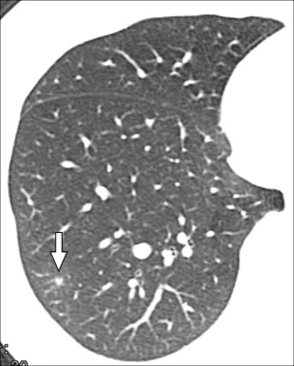

CT主要表现为三处非常细小的渗出(图1-3箭头所示):

图2

回到这个小护士病例,根据水痘表现,加上影像学表现为GGO、小结节周围GGO,应该比较符合的,可以临床诊断为水痘肺炎。但本病例仅发现3个小病灶,没有广泛累及,推测原因可能是先前可能接种过水痘疫苗,肺部累及较轻。

本例患者是因筛查新冠CT检查而意外发现的轻微的水痘肺炎,病程中并无明显咳嗽、气急与呼吸困难。当然此例水痘肺炎是建立在临床诊断基础之上,有必要进一步跟踪随访。